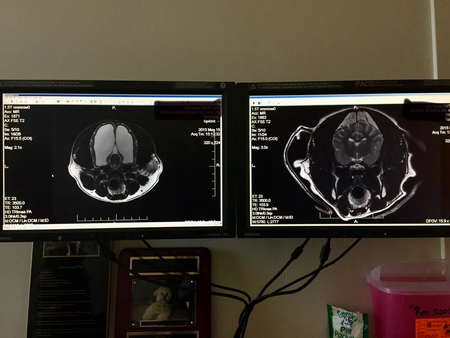

A confirmação veio com a ressonância magnética, que revelou que a cadela tinha hidrocefalia severa, em que quase todo o espaço dentro do crânio estava ocupado por líquido, restando apenas uma pequena parte de tecido cerebral funcional. A imagem comparativa com um cérebro canino considerado normal torna esse contraste ainda mais impactante:

ressonância magnética do cachorro A esquerda, uma imagem do cérebro da cadela. O branco visto na ressonância magnética era líquido. A esquerda, uma comparação com um cachorro "normal". Créditos: Reprodução